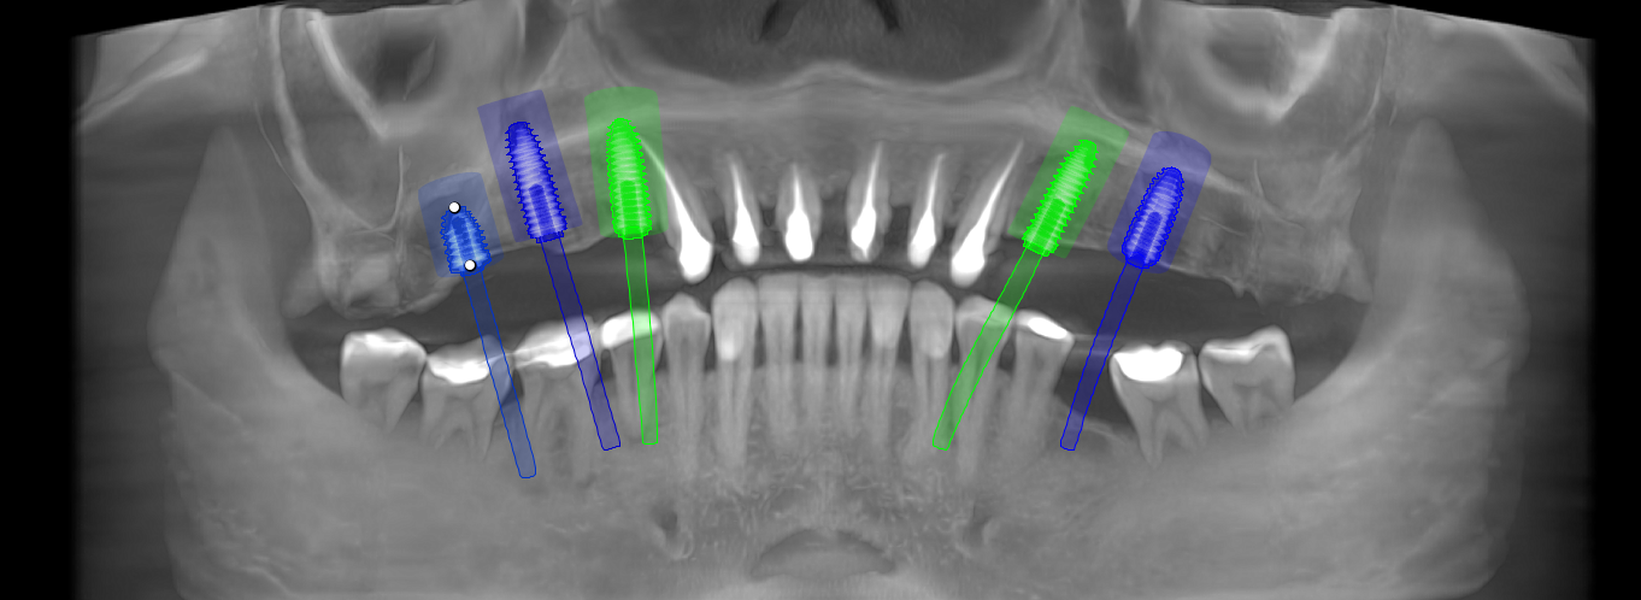

Reabilitarea complexă în stomatologie presupune refacerea completă a sistemului dentoalveolar, atât din punct de vedere funcțional, cât și estetic. Procesul începe cu o examinare detaliată a cavității bucale, interpretarea investigațiilor imagistice (CBCT), evaluarea musculaturii, articulațiilor temporomandibulare și a parametrilor estetici.

Tomografii (CBCT)

Caz 2